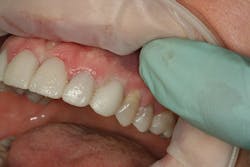

At the beginning of the impression appointment, the provisionals were approved for fit and esthetics with a particular focus on emergence profile of the implant provisionals. Profound anesthesia was achieved and the bisacrylic provisionals were removed. The preparations were cleaned with chlorhexidine (Consepsis, Ultradent) and the abutments were once again removed (figure 10). The open-tray impression copings were then tried in, their seat confirmed radiographically, and then modified into custom impression copings with flowable composite (figures 11-14). Once appropriate tissue support was confirmed, the open-tray master impression was made with a heavy and light body wash technique using vinyl polysiloxane impression material (Honigum, DMG America) (figure 15). Following the master records, the provisional abutments and bisacrylic provisionals were replaced until the seat appointment.

Figure 11

Figure 12

Figure 13

Figure 14